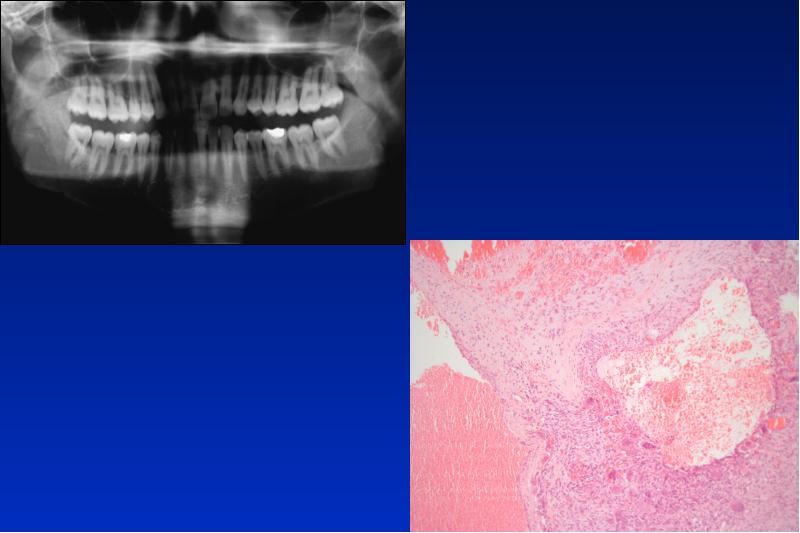

- 85. Cherubismus autosomal dominant vererbtes Krankheitsbild mit symmetrischer Kieferauftreibung im Kindesalter und